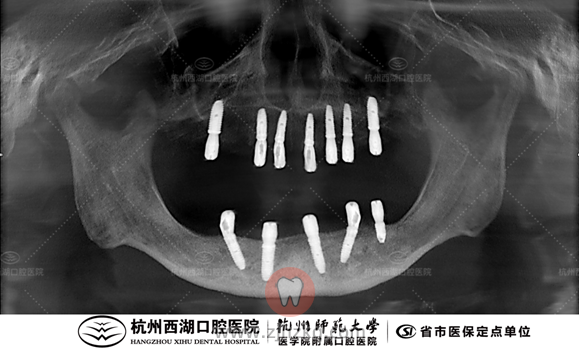

上个月术前CBCT照如下